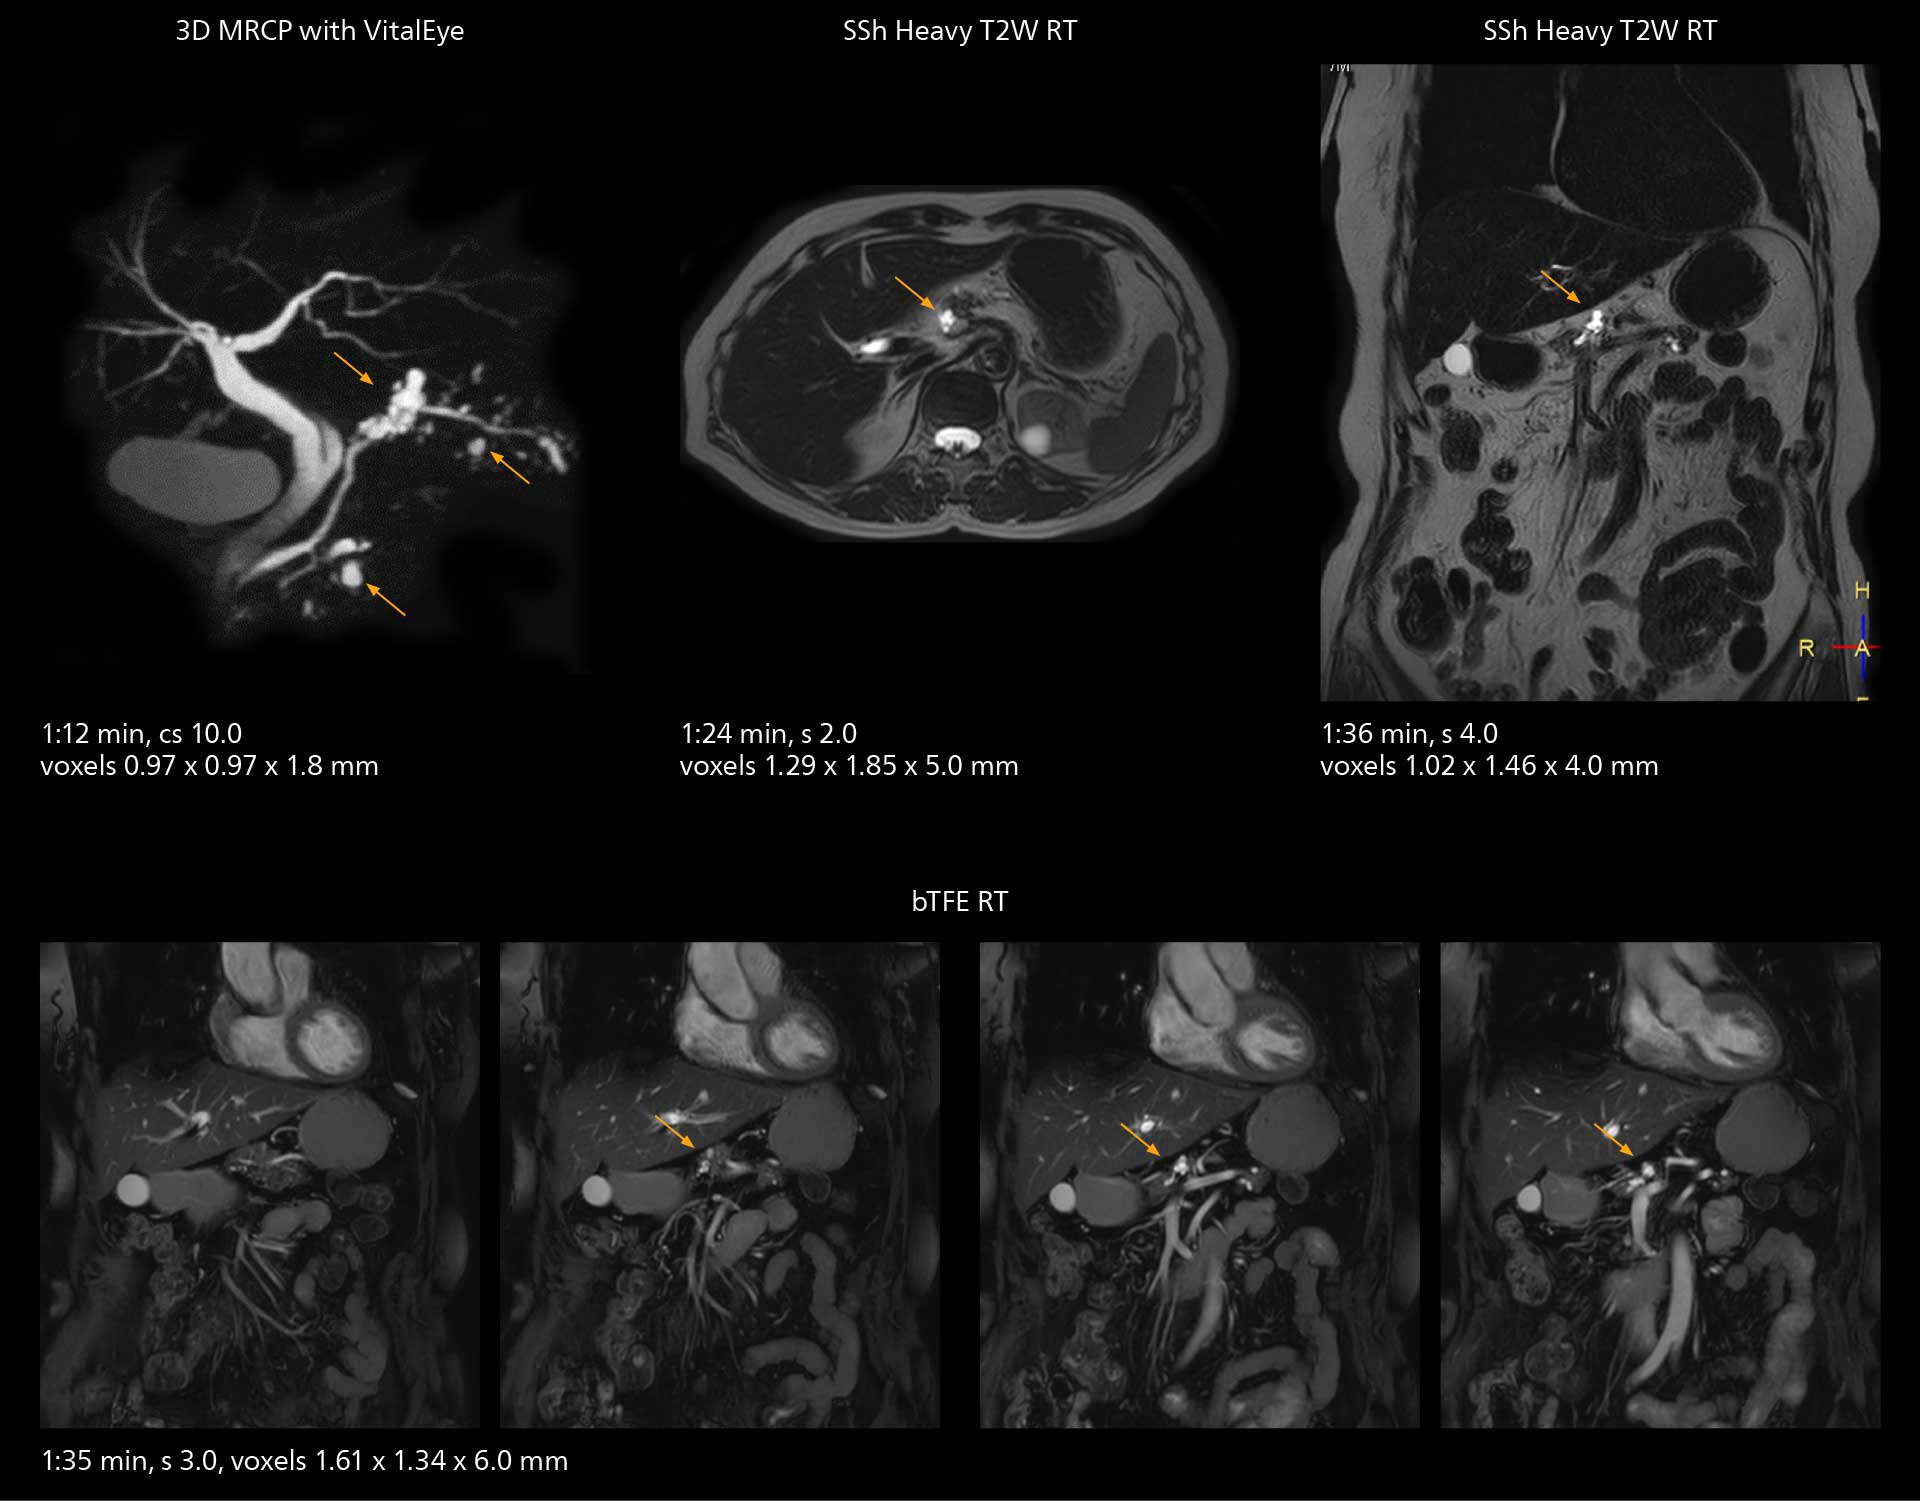

MRCP

With SmartPath to Elition X, the MRCP examinations at Sannodai Hospital benefit from VitalEye: respiratory synchronization is possible without respiratory belt positioning and image quality is excellent.